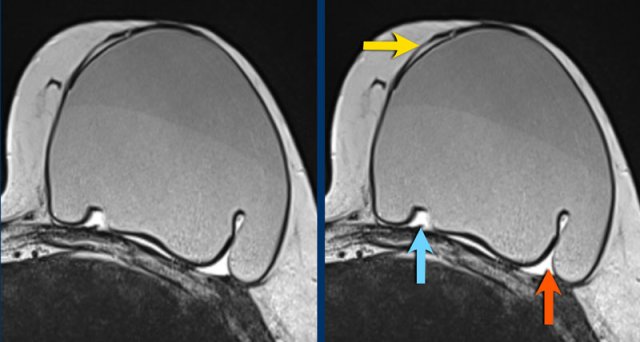

Here another example of the different presentations of intracapsular rupture with silicone outside the envelope, but within the capsule.

- subcapsular line (yellow arrow)

- nose sign (blue arrow)

- teardrop sign (red arrow)